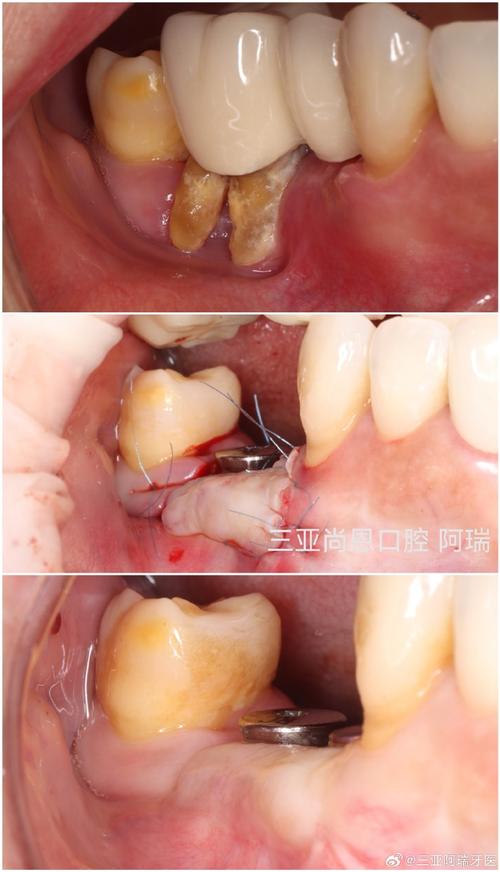

翻瓣暴露骨缺损

沿牙龈做内斜切口或梯形切口,翻开黏骨膜瓣,充分暴露牙槽骨缺损区,彻底清除肉芽组织、炎性上皮及牙根表面的牙石、菌斑(根面平整是植骨成功的关键)。

植骨材料放置与固定

根据缺损类型选择植骨材料(详见下表),将其紧密填入骨缺损区,避免死腔;对于较大缺损,可覆盖生物膜(如胶原膜、聚乳酸膜)引导骨再生,防止软组织长入。

缝合与术后处理

黏骨膜瓣复位,用可吸收缝线(如 Vicryl)间断缝合,压迫止血;术后给予抗生素(如阿莫西林)预防感染,指导患者使用漱口液(如氯己定),1周后拆线。